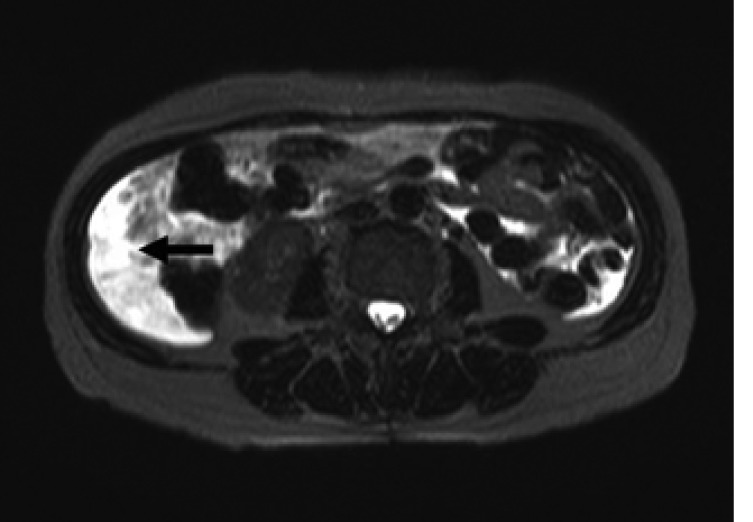

Laboratory data on admission were within normal limits. A chest X-ray (Figure 1A) and CT scan (Figure 1B) showed massive right pleural effusion, and ultrasonography, CT and MRI scans revealed a 6×10×12 cm in sized intrapelvic huge solid mass, including cystic components involving both adnexae and the uterus, and a moderate amount of intra-abdominal fluid collection (Figure 2, 3). The MRI and CT scans showed no evidence of a metastatic disease involving the lymph nodes, bone or abdominal organs. The serum CA125 concentration was 82.49 U/mL (normal, 0~35 U/mL). The serum levels of carcinoembrionic antigen (CEA) and carbohydrate antigen 19-9 (CA19-9) were normal. A cytological examination of both the ascites and pleural fluid showed no signs of malignant cells. An explorative laparotomy was performed based on the suspicion of ovarian cancer. Serous ascites, a moderately enlarged uterus and a large right ovarian mass were found, but there were no signs of metastatic spread. A total abdominal hysterectomy (TAH) was performed, with a bilateral salpingo-oophorectomy (BSO), partial omentectomy and pelvic lymph nodes sampling. During the operation, the ovarian tumor ruptured in the pelvic cavity and 2,500 mL of serous ascites were drained during the laparotomy. Due to the right pleural effusion, a trocar tube was inserted into the right thorax, with a total of 650 ml of serous fluid collected.

Figure 2

Magnetic resonance imaging on the T2-weighted images showing an intra-abdominal fluid collection (arrow).